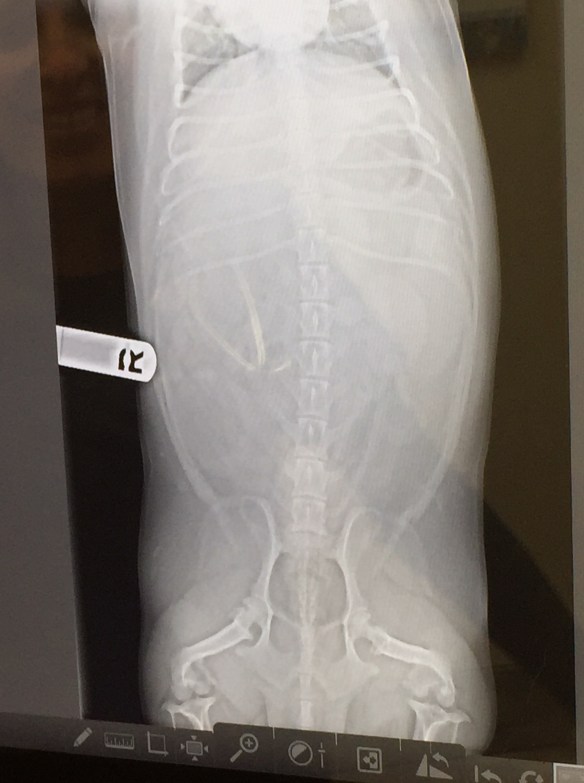

Do you know what my x-rays revealed?

I don’t know what “gas in the fundus” is, but it isn’t exactly pleasant!

I was prescribed a four-pack of Cerenia and pills to quell the desire of my intestinal tract to pump waste materials through my plumbing every 45 minutes. Oh, and a bonus shot to stop vomiting. Oh, and some gravy flavored sprinkle-ings that are fortified with bacterium.